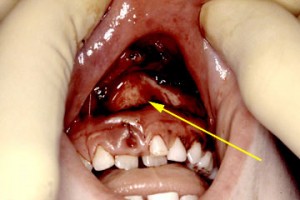

avulsed tooth © kravitzorthodontics.blogspot.com

Soft tissues injuries to the mouth

The simplest and most common type of soft tissue injury is bruising. This will often be present without any dental involvement. Treatment is symptomatic. However be careful to check in the depths of the inner mouth for any deep soft tissue wounds or degloving type injuries.

Often a full-thickness laceration of the lower lip can be undetected because of the natural contours of the soft tissues or the tentative examination of an upset child. If there has been dental injury, always look for tooth remnants in the lips.